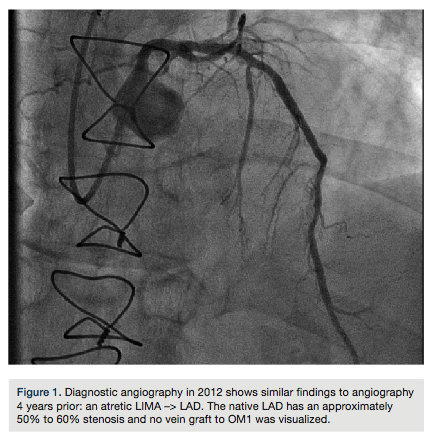

A previous angiography in 2008 showed an atretic LIMA –> LAD. The native LAD had an approximately 50% to 60% stenosis and no vein graft to OM1 was visualized. She underwent diagnostic angiography with similar angiographic findings (Figure 1); however, given

her symptoms, fractional flow reserve (FFR) measurement of the LAD was recommended for further assessment.